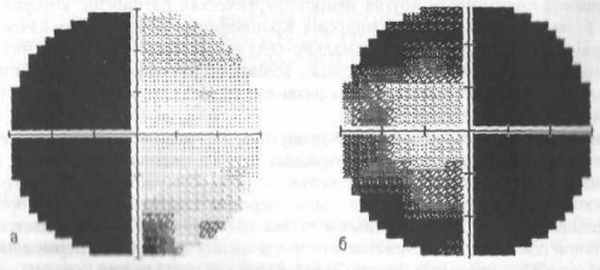

Битемпоральная гемианопсия ( по данным автоматической статической периметрии)

Битемпоральная гемианопсия одна из основных составляющих хиазмального синдрома, где величина гемианопического дефекта различная, oт начального сужения границ поля зрения в верхневисочном, реже в нижневисочном квадранте, до полного выпадения половин поля зрения. При хиазмальном синдроме острота зрения может оставаться практически нормальной, несмотря на полную битемпоральную гемианопсию. Это более характерно для пациентов с аденомой гипофиза. Хиазмальный синдром сопровождается развитием первичной нисходящей атрофии зрительного нерва, что происходит в результате страдания зрительных волокон на уровне хиазмы. В клинической практике, однако, чаще встречается хиазмальный синдром в сочетании со снижением остроты зрения. Снижение остроты зрения свидетельствует о воздействии процесса, помимо хиазмы, на дистальные отделы зрительных нервов.

Хиазмальный синдром возникает при поражении хиазмы (зрительного перекрёста). Организация зрительных волокон хиазмы ответственна за характер дефектов поля зрения, развивающихся при её поражении. Поражение центрального отдела хиазмы, где располагаются перекрещивающиеся зрительные волокна, проявляется гетеронимной (разноименной) битемпоральной гемианопсией. Битемпоральная гемианопсия - дефект в височных половинах поля зрения обоих глаз.